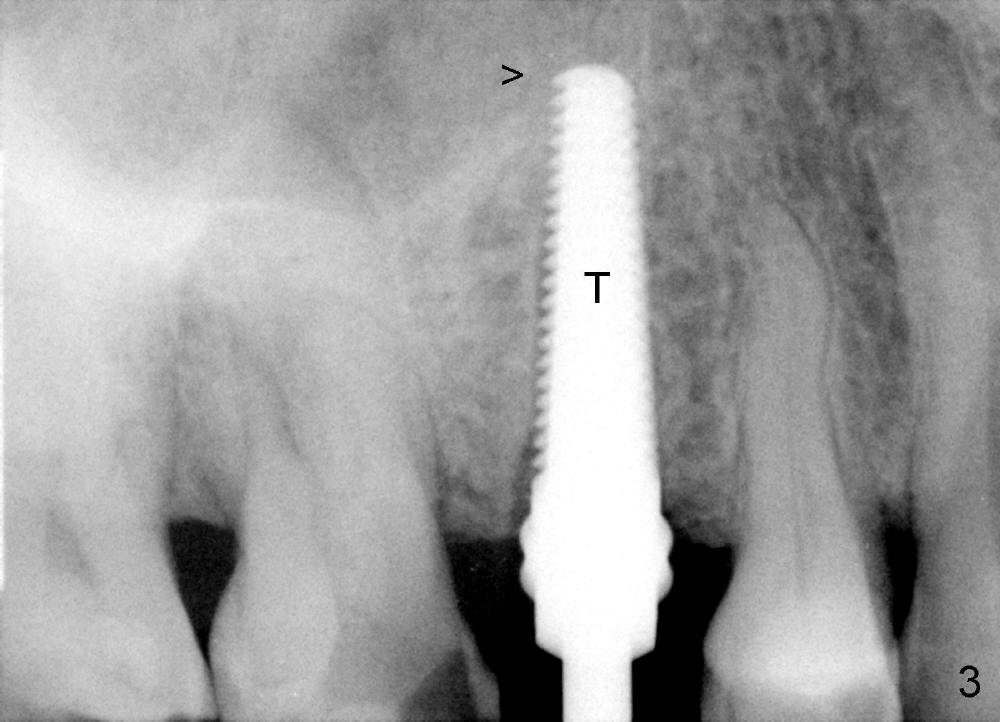

A 72-year-old man is a bruxer with #3 cusp fracture with chronic periapical radiolucency (Fig.1 *) and #4 acute crack.  It appears reasonable to take care of emergency (#4 extraction and immediate implant (Fig.3-7: 4.5x20 mm, 45 Ncm)) followed by root canal therapy or extraction for #3.  Eight (Fig.8) and 14 (Fig.9-11) days postop, the patient is doing fine and the wound heals normally.  But he does not agree any treatment for #3, since it is asymptomatic in spite of a fistula associated with the tooth (Fig.8,9 >).  Three months postop, the patient is still asymptomatic and is ready for #4 restoration since the tooth #28 cracks.  Follow-up PA shows the persistent distal gap (Fig.12 >, as compared to Fig.4), accompanied with crestal bone resorption (*).  Clinically the implant has mild mobility and light tenderness. The patient still refuses #3 treatment. It appears that the implant has failed to osteointegrate.  In brief, do not place an immediate implant next to active infection.